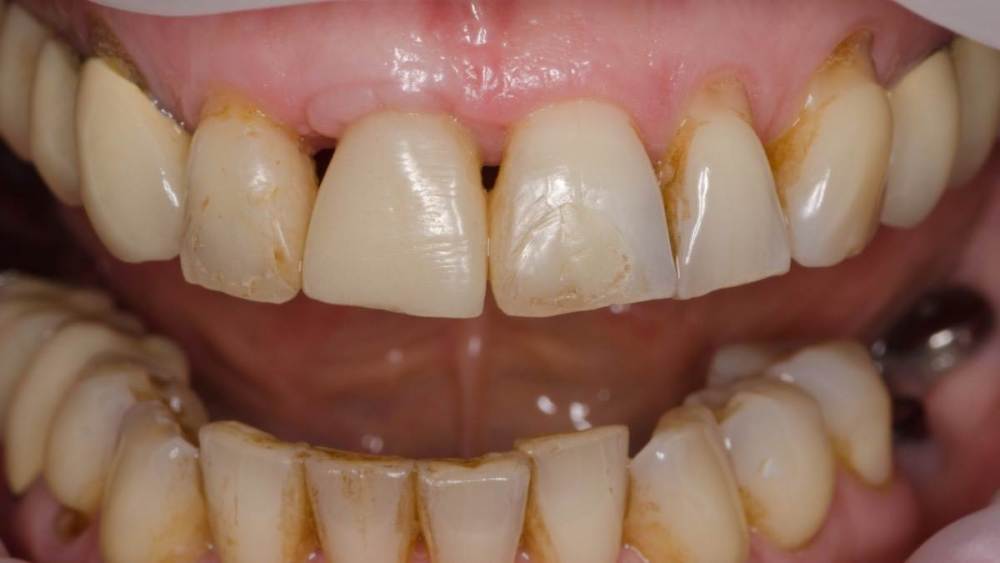

Владмир Опубликовано 20 марта, 2023 Автор Поделиться Опубликовано 20 марта, 2023 Здравствуйте коллеги. Работе 10 лет. Фото начальных этапов добавил 7 1 2 Ссылка на комментарий